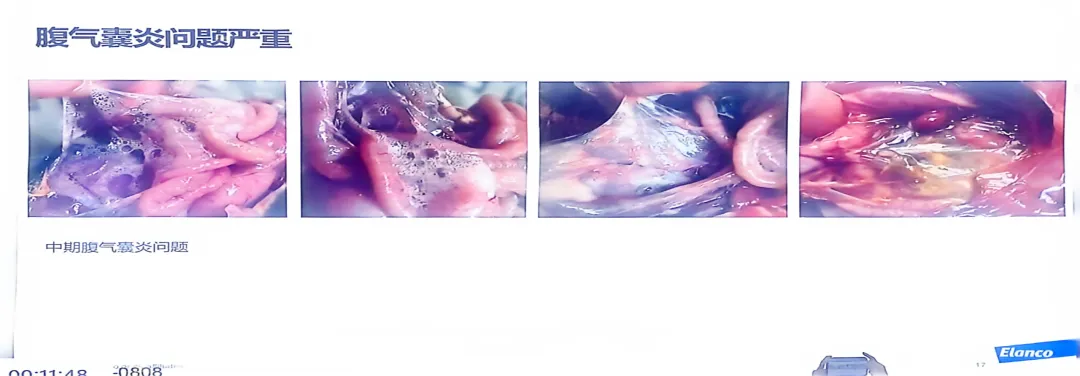

>精品课件!!鸡支原体的危害及防控思路